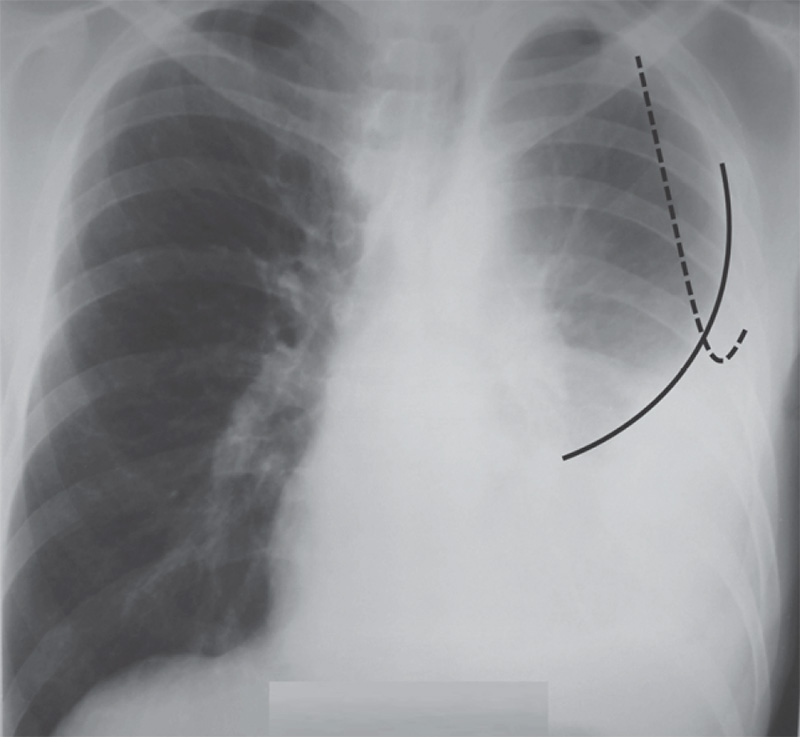

Рентгенологическая картина при большом накоплении жидкости в плевральной полости характеризуется субтотальным или тотальным затемнением легочного поля, эти изменения также рассмотрены в статье «Рентгенография: Затемнения или Просветления легочного поля» (рисунок 1, 2). Обусловленное содержимым в плевральной полости затемнение располагается в области реберно-диафрагмального синуса и нижних отделах легочного поля; в случае увеличения количества содержимого площадь затемнения увеличивается, распространяясь снизу-вверх (если содержимое рассасывается, площадь затемнения уменьшается в обратном направлении – сверху вниз).

При гидротораксе затемнение более интенсивное и однородное, на его фоне часто не визуализируются (или плохо визуализируются) элементы легочного рисунка и корень легкого, при левосторонней локализации затемнение перекрывает тень сердца, сливаясь с ней. Купол диафрагмы плохо дифференцируется (или вообще не определяется). Верхняя граница затемнения имеет дугообразную форму и располагается по направлению наружного отдела легочного поля вниз к срединной тени (контуры этой границы могут быть не четкие). Прозрачность легкого над этой границей может снижаться (это обусловлено патологическими изменениями в самом легком, например, при пневмонии, или сдавлением легкого содержимым в плевральной полости). Важный признак гидроторакса – смещение срединной тени в противоположную от зоны поражения сторону (такое смещение хорошо определяется при накоплении большого объема жидкости в плевральной полости).

Если в плевральной полости скапливается небольшое количество выпота, на рентгенограмме определяется затемнение только в области синусов. В этом случае выпот сначала накапливается в заднем синусе (определяется на рентгенограмме, выполненной в боковой проекции), потом – в реберно-диафрагмальном синусе (определяется на рентгенограмме, выполненной в прямой проекции) (рисунок 1, 2). В норме определяется острый «угол» между диафрагмой и стенкой грудной клетки в области синусов. При накоплении небольшого количества содержимого этот «угол» сглаживается, синус становится «неглубоким».

Рисунок 1. Малый гидроторакс (схематическое изображение рентгенограммы, выполненной в прямой и боковой проекциях)

Рисунок 5. Большой гидроторакс слева. Определяется верхняя граница плеврального выпота (см сплошную линию). Штриховой линией обозначен контур лопатки

Кроме этого, ориентируясь на задние отрезки ребер по подмышечной линии (на рентгенограмме определяются примерно в области наружных отделов ребер; в месте «перекрестка» теней передних и задних отрезков ребер), можно обозначить уровень верхней границы выпота. В этом случае малый гидроторакс не достигает заднего отрезка VII ребра; средний гидроторакс – граница выпота определяется между задними отрезками V-VII ребер; большой гидроторакс – граница содержимого определяется выше заднего отрезка V ребра (рисунок 6).